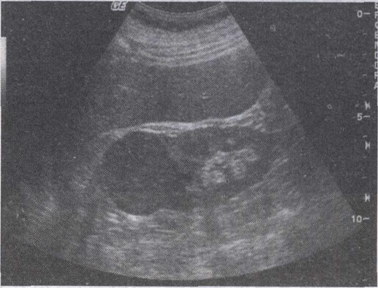

48.男,45岁,因出现无痛性血尿半月余就诊,根据超声声像图提示,最可能的诊断是